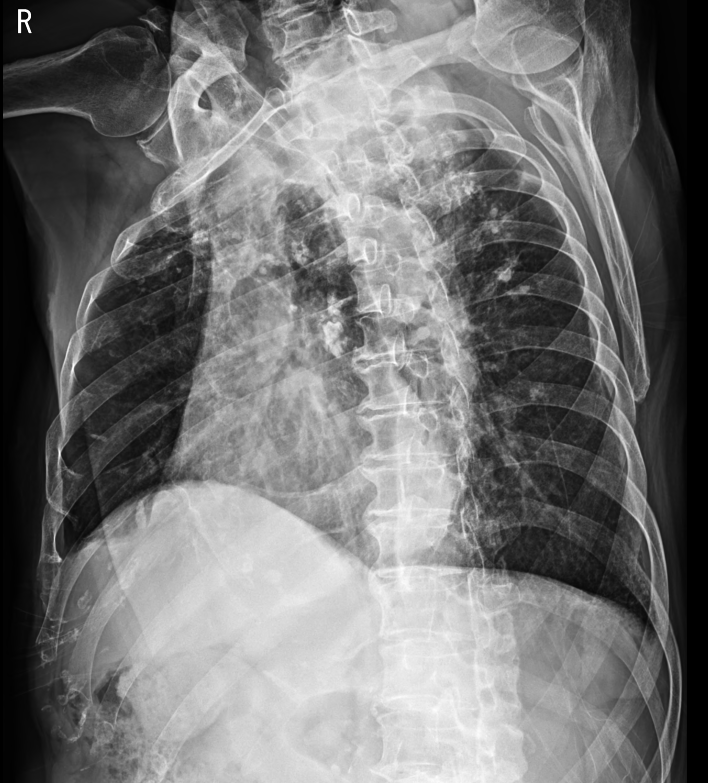

3. Rib series ; 갈비뼈 골절을 확인하는 방법

갈비뼈 골절을 확인하기 위해 촬영하게 되는 chest x ray이다.

갈비뼈(rib)는 위아래로 근육이 잘 잡아주고 있는 구조로 이뤄져 있다. (돼지고기 등갈비를 생각하면 이해하기 쉽다.)

가만히 서있는 경우엔 주변 근육이 갈비뼈를 잘 잡아주고 있어 골절이 있는 부분도 어긋나는 경우는 매우 드문 일이다. 때문에 일반적인 chest pa로는 갈비뼈 골절을 찾아내는 것이 쉽지만은 않다.

하지만 좌우로 몸을 굽혀 갈비뼈 사이 공간을 벌어지게 만든다면 좀 더 쉽게 갈비뼈 골절을 진단할 수 있게 된다.